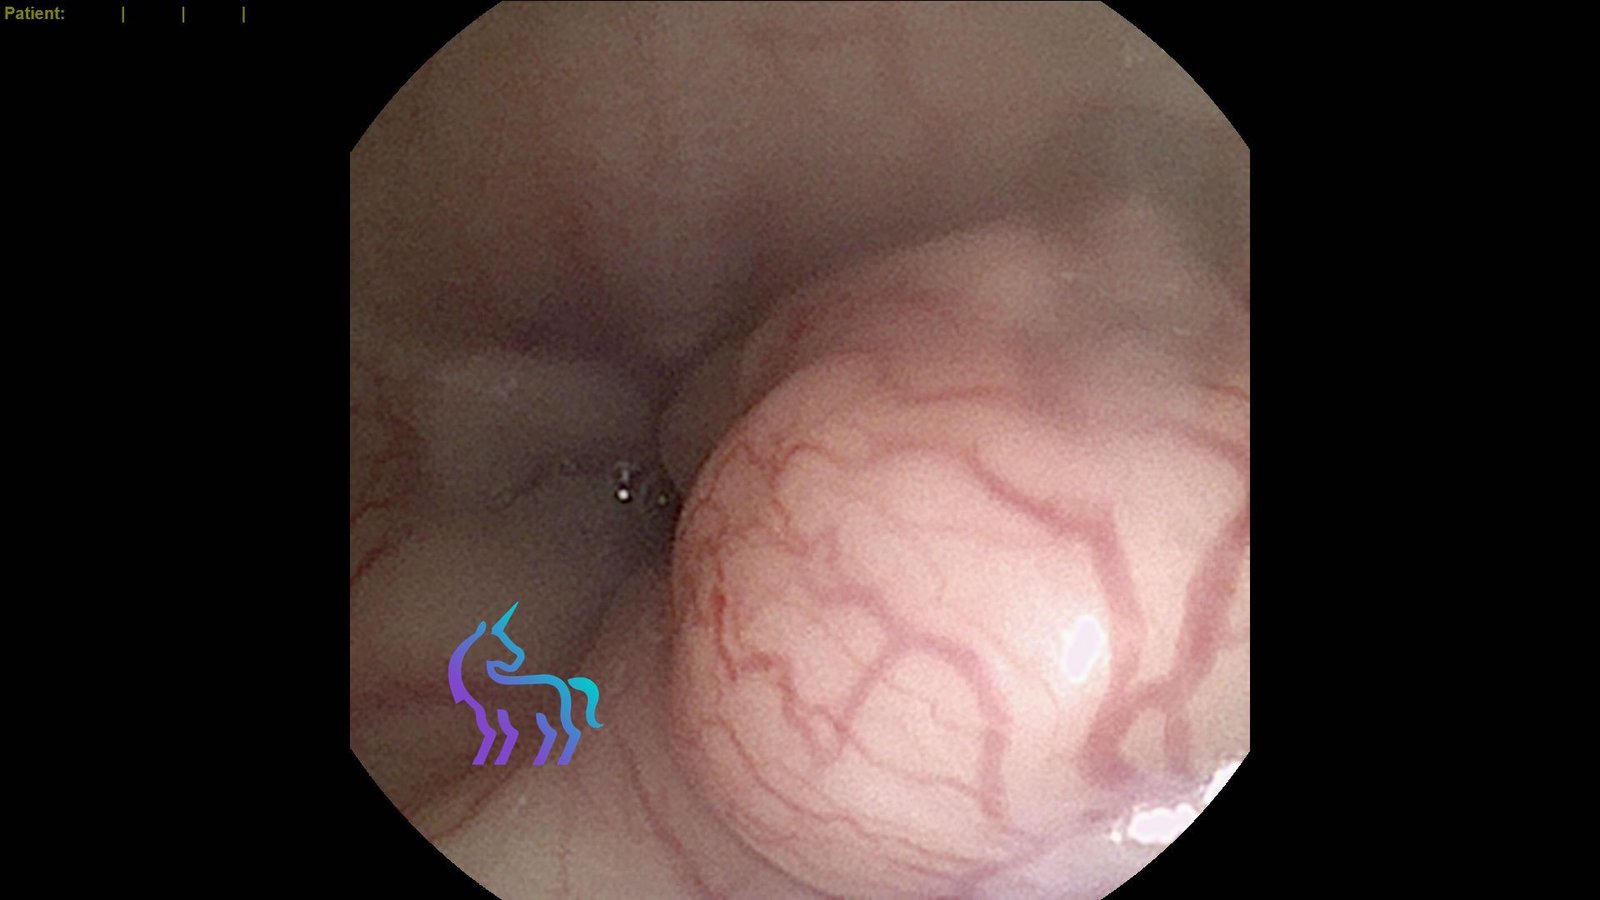

Vue endoscopique de la muqueuse intestinale présentant un aspect inflammatoire chronique.

Endoscopie digestive : Diagnostic d’Entéropathie Chronique

Espèce : ChienLors de l’endoscopie digestive, la muqueuse intestinale présente un aspect inflammatoire, compatible avec une atteinte chronique.

Des biopsies ont été réalisées pendant l’examen afin d’obtenir un diagnostic fiable par analyse histologique.

Diagnostic retenu : L’analyse conclut à une entéropathie chronique, permettant d’adapter la prise en charge (alimentation, traitements ciblés et suivi).